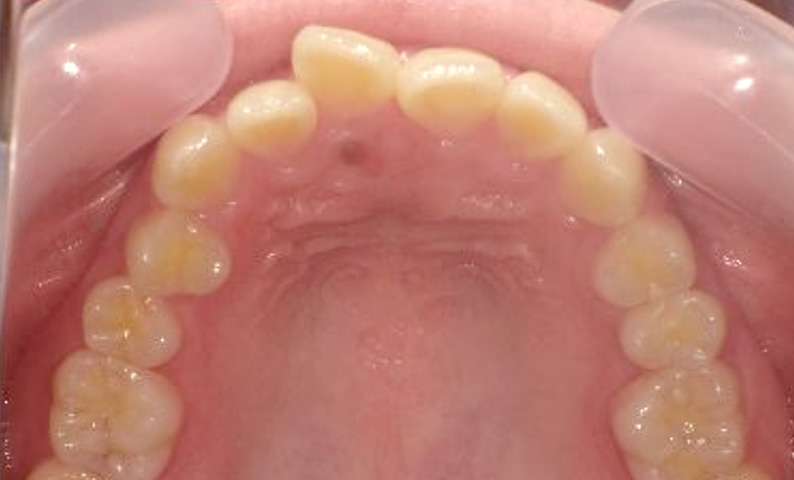

症例_023 上顎だけの部分矯正

治療期間:9ヶ月金額:30万円+税女性前歯のガタガタ上の前歯だけ

| Before | After |

|---|---|

|